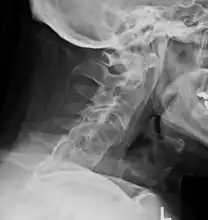

Lateral X-ray of the mid back in ankylosing spondylitis

Lateral X-ray of the neck in ankylosing spondylitisImaging

X-rays

The earliest changes demonstrable by plain x–ray shows erosions and sclerosis in sacroiliac joints. Progression of the erosions leads to widening of the joint space and bony sclerosis. X-ray spine can reveal squaring of vertebrae with bony spur formation called syndesmophyte. This causes the bamboo spine appearance. A drawback of X-ray diagnosis is the signs and symptoms of AS have usually been established as long as 7–10 years prior to X-ray-evident changes occurring on a plain film X-ray, which means a delay of as long as 10 years before adequate therapies can be introduced.[19]